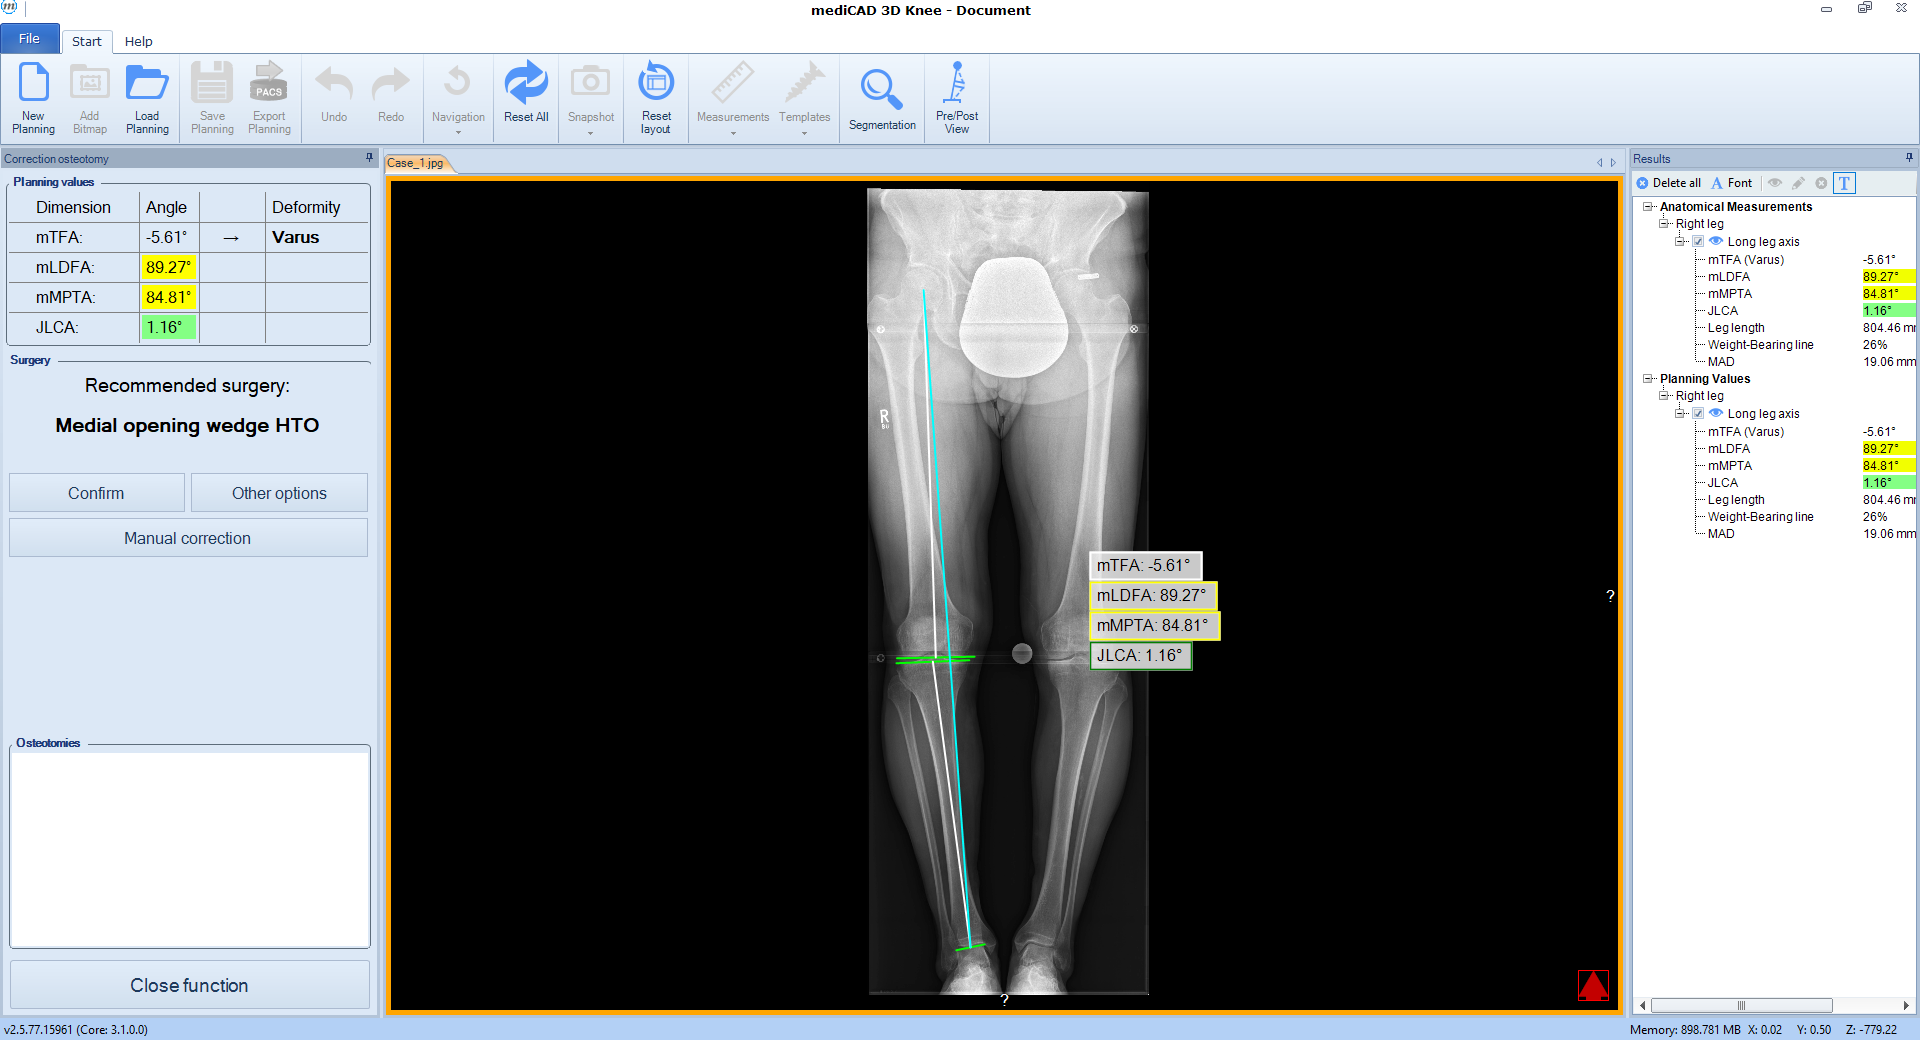

Following the deformity analysis, the software automatically recommends a surgical procedure, eg, medial opening wedge high tibia osteotomy, depending on the type of deformity (Fig 2). The user can follow the proposed procedure or choose individual options.